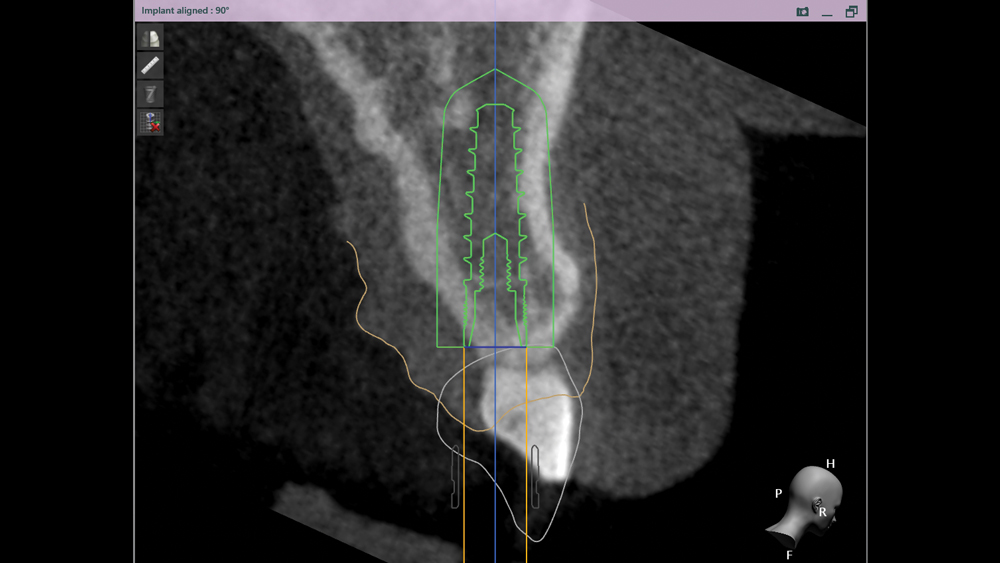

The following case illustrates the efficient, straightforward clinical workflow for placing Hahn Tapered Implants via guided surgery. A digital treatment plan is developed in which a 3.5 mm implant is positioned to support the ideal prosthetic outcome. An immediate provisional crown is designed in concert with the surgical guide and delivered at the time of surgery, helping to produce a predictable, highly esthetic restoration for a demanding case in the smile zone.